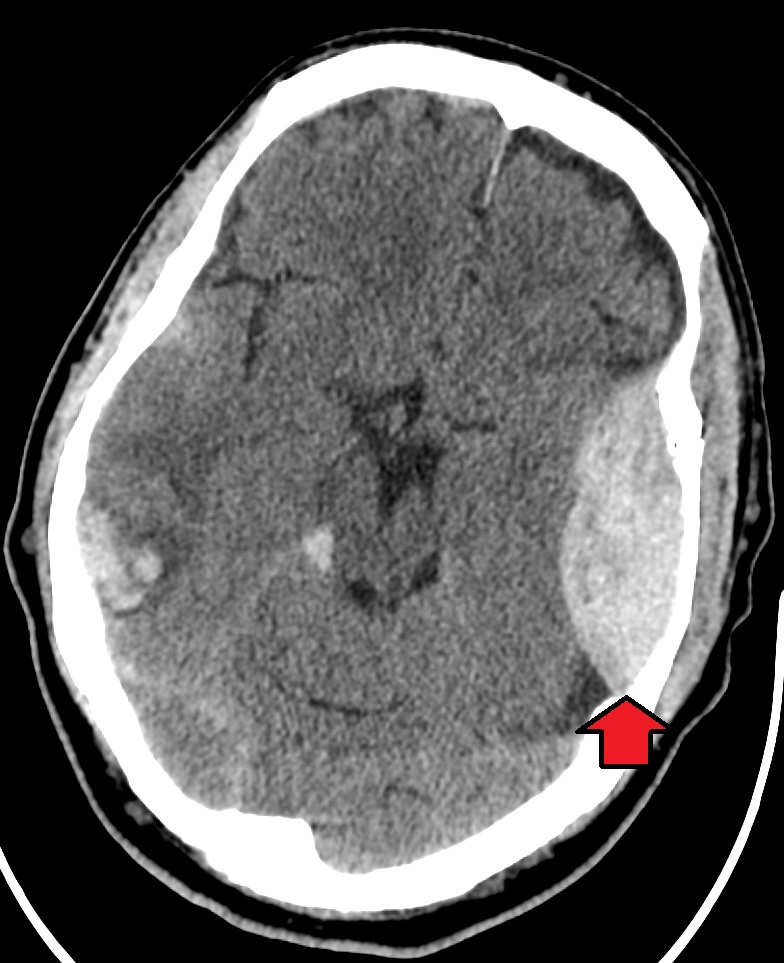

Radiology of subdural hematomas reveal a lesion with a crescent shape.